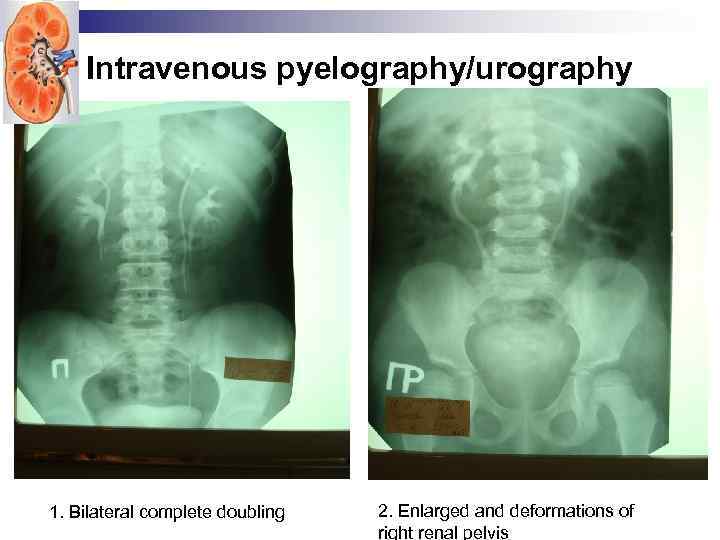

Intravenous pyelography/urography 1. Bilateral complete doubling 2. Enlarged and deformations of right renal pelvis

Intravenous pyelography/urography 1. Bilateral complete doubling 2. Enlarged and deformations of right renal pelvis